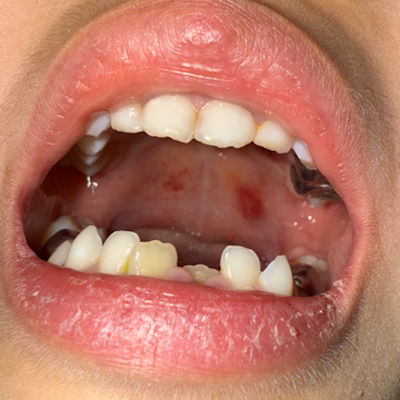

During a routine recall exam for a pediatric patient, the dentist noted an unusual “growth” affecting the right anterior mandible.